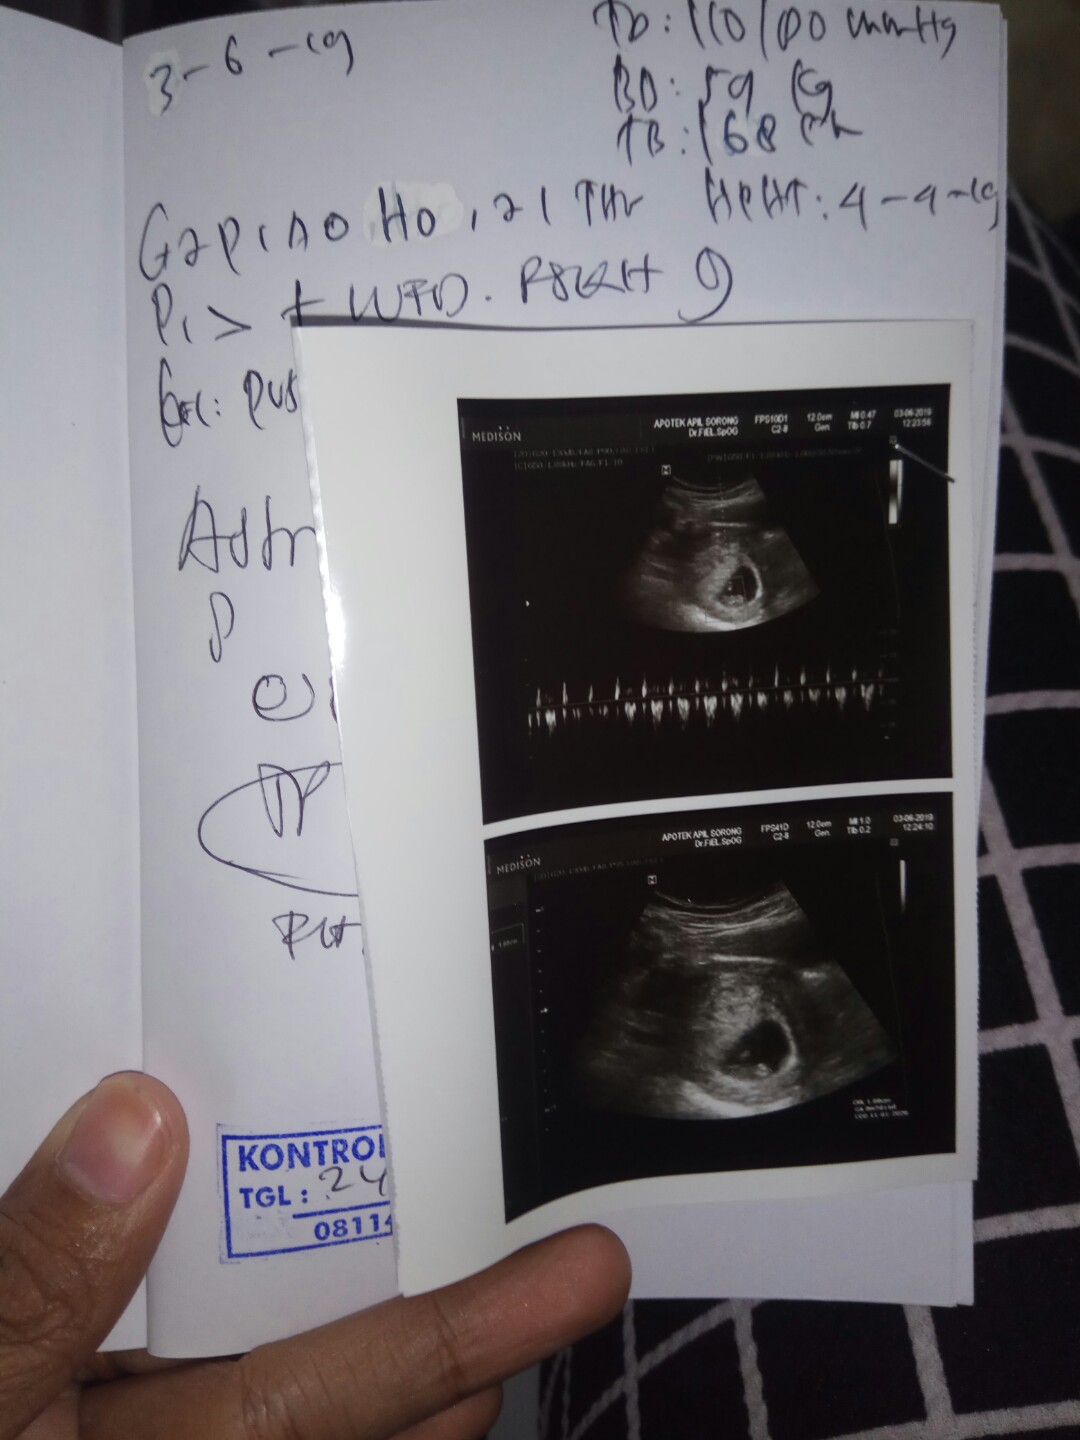

mungkin normal bund tiap ormg beda2 saya 7 wek 2 day udah keliatan janin n ddj